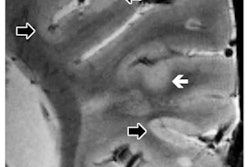

More specifically, with 7-tesla MRI, BWH clinicians can see minute central veins within white-matter plaques of the brain's parenchyma. Gray-matter and cortical lesions are also identifiable at 7 tesla to evaluate these two conditions, he added.

"If we can find the abnormality in the brain of a patient having seizures and the brain can be surgically resected, we can potentially cure a patient of their seizures," he said. "Many of these little areas that cause seizures are focal cortical dysplasias that tend to be very small and very subtle. Many of them are literally invisible on 1.5-tesla and 3-tesla scanning."